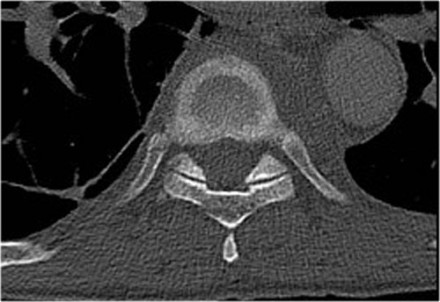

Burst fracture

This is the severe variant of a compression fracture with higher risk of neurologic deficits.

A burst fracture gets 2 points for morphology in the TLICS.

Retropulsion of posterosuperior vertebral body fragment

Retropulsion of a fragment is the typical feature of a burst fracture and distinguishes it clearly from a simple compression fracture.

Sagittal fracture of vertebral body and posterior element

A sagittal fracture of the vertebral body and a sagittal posterior element fracture is seen in respectively 90% and 85% of cases of burst fracture cases.